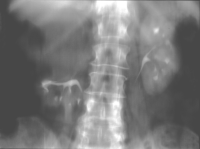

Die Patientin wurde beim Urologen wegen seit 3 Wochen persistierender Flankenschmerzen rechts vorstellig. Der Untersuchungsbefund zeigte als Auffälligkeit ein klopf- und druckschmerzhaftes Nierenlager rechts. Der Urinstatus wies keine Besonderheiten auf. Sonographisch fand der Urologe eine ca. 11 cm große einfache Nierenzyste rechts, die bis in das Nierenbecken reichte. Mit dem anschließend durchgeführten i.v.-Pyelogramm konnte eine Abflussbehinderung aus dem Nierenhohlraumsystem ausgeschlossen werden. Es waren jedoch glatt berandete, zystentypische Kelchausziehungen der oberen und mittleren Kelchgruppe zu erkennen. Der Urologe stellte die Patientin stationär in der Klinik vor. Zum Ausschluss eines eventuell vorliegenden zystischen Karzinoms wurde ein CT des Abdomens durchgeführt. Hier fand sich eine große, unkomplizierte Zyste, die die Niere verdrängte (Abbildung 4).